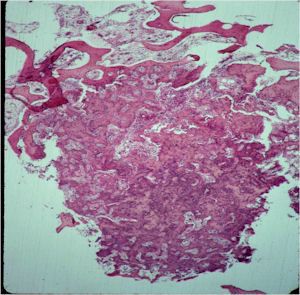

Gross Pathology

- The nidus is distinct oval/round and reddish from vascularity;

- It is well circumscribed and easily separated from surrounding bone;

- The nidus is usually less than 1 cm but may be up to 2 cm;

- The nidus may have a variable consistency depending on the extent of mineralization

- Friable, soft and granular to densely sclerotic

Microscopic Pathology

- The nidus of an osteoid osteoma consists of vascularized fibrovascular stroma and trabeculae of immature woven bone

- Nidus is sharply demarcated from surrounding reactive bone and there is an abrupt zone of transition between normal bone and the osteoid osteoma. There is no permeation of the lesion through the surrounding reactive trabeculae of bone,

- The trabeculae are uniformly lined by plump, uniform, active osteoblasts (“Osteoblastic Rimming)

- Osteoclasts may be prominent

- Mature nidus consists of more heavily calcified trabeculae of woven bone and osteoid

- No abnormal mitoses